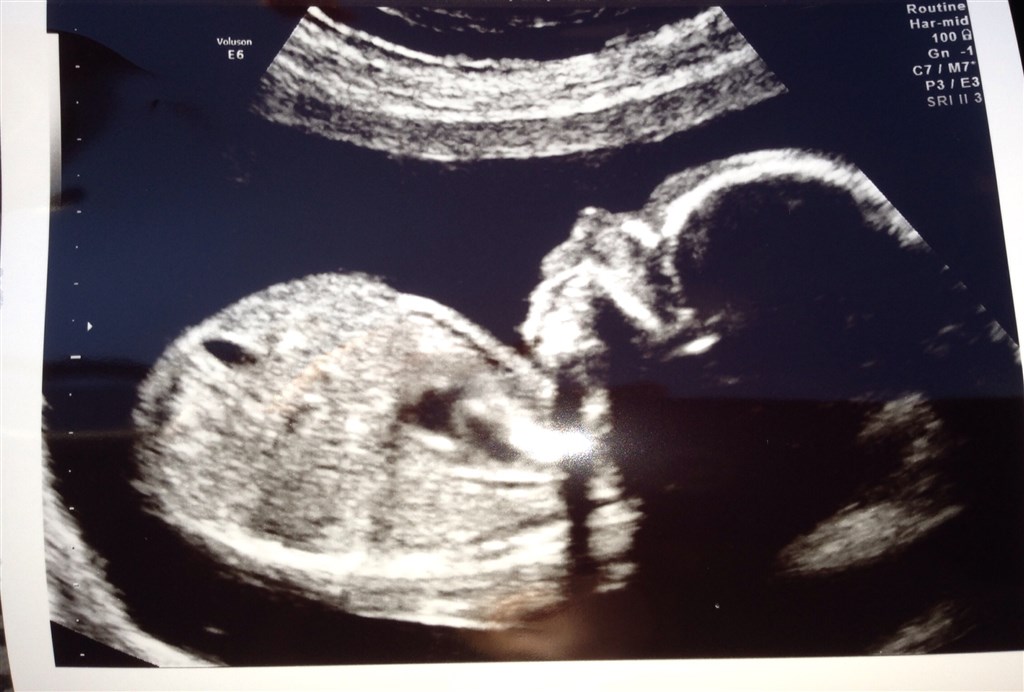

Flertallet har talt, men babyen i maven har vist sig at være en LILLESØSTER.

Scanningen gik rigtig godt selvom hun drillede lidt, den lille bandit. Hun ville ikke vise ansigt og lå med samlede ben det meste af tiden.

Heldigvis havde vi en sød og tålmodig jordemoder, som ikke gav så let op, og fik gennemscannet alt inkl. kønnet.

Da hun til sidst kunne se kønnet var hun ikke i tvivl og det er også skrevet på vandrejournalen, men det er stadigvæk ikke helt gået op for os endnu.

Men her er hun.